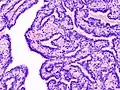

| Histopathology of intraductal papilloma of the breast by excisional biopsy. Immunostaining for p63 protein. | |

Histopathology of intraductal papilloma of the breast by excisional biopsy. Hematoxylin and eosin stain. -

Histopathology of intraductal papilloma of the breast by excisional biopsy. Immunostaining for alpha-smooth muscle actin.